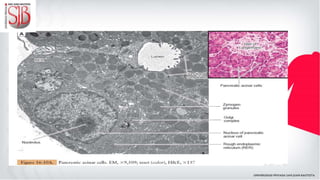

El páncreas presenta una zona endocrina y otra exocrina. Los acinos pancreáticos

presentan las células centro acinares.

PÁNCREAS El páncreas presentauna zona endocrina y otra exocrina. Los acinos pancreáticos presentan las células centro acinares. Entre las sustancias producidas tenemos el tripsinógeno (se activa en tripsina al mezclarse con la bilis).